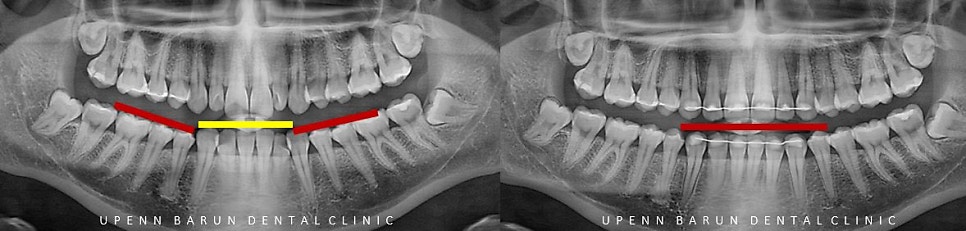

정상적인 교합의 경우 오른쪽 사진과 같이

윗니가 아랫니를 1/4정도 덮고 있는것이 일반적이지만

왼쪽 사진처럼 반 이상 과도하게 덮고 있는경우를

'과개교합'(Deep Bite) 라고 합니다.

과개교합이 심한경우

정면에서 바라볼 때 아랫니가 잘 보이지 않습니다.

또 아랫니가 윗쪽 잇몸을 누르며

통증이 유발되거나 잇몸 퇴축이 일어날 수 있습니다.

또한 앞니끼리 면을 끊거나 자르는게 쉽지 않고

턱관절에도 좋지 않은 영향을 줄 수 있습니다.

과개교합의 경우

교정을 통해 치열개선뿐만 아니라

윗니, 아랫니의 맞물리는 위치를 이동시켜

치아의 기능과 심미적인 부분을 개선시킬 수 있습니다.